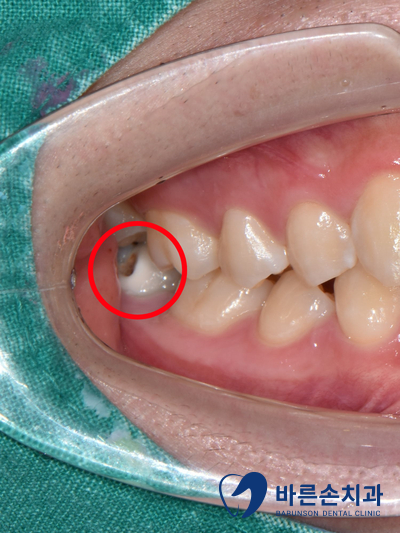

사진 상으로 보면

어금니 바깥쪽면으로 색이 변해있고

충치가 생겨 있는 것이 보입니다.

X-ray 상에서도

까맣게 충치가 신경까지 닿아있는 것을 확인 할 수 있습니다.